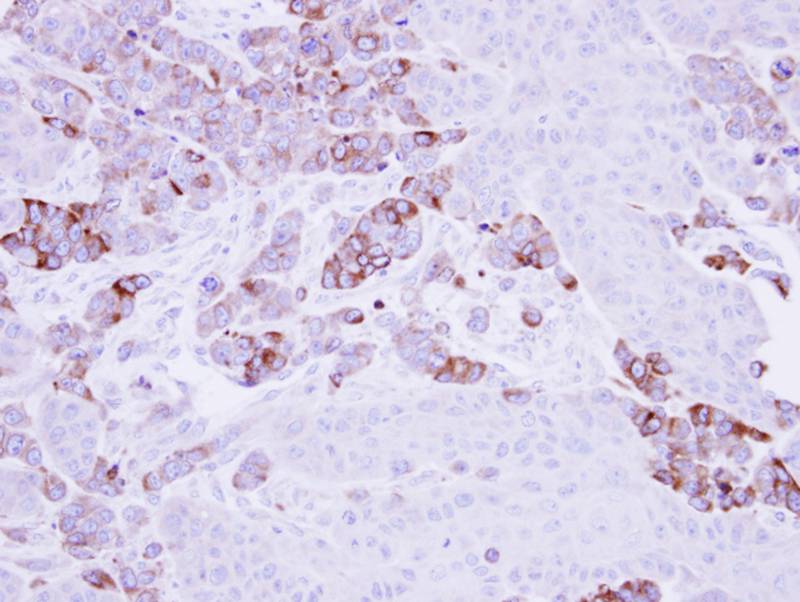

Immunohistochemical analysis of paraffin-embedded SG xenograft, using Epoxide hydrolase 1 antibody at 1: 500 dilution.